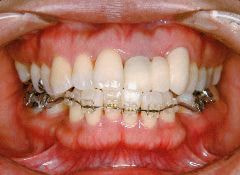

治療例1 (インプラント補綴+矯正)